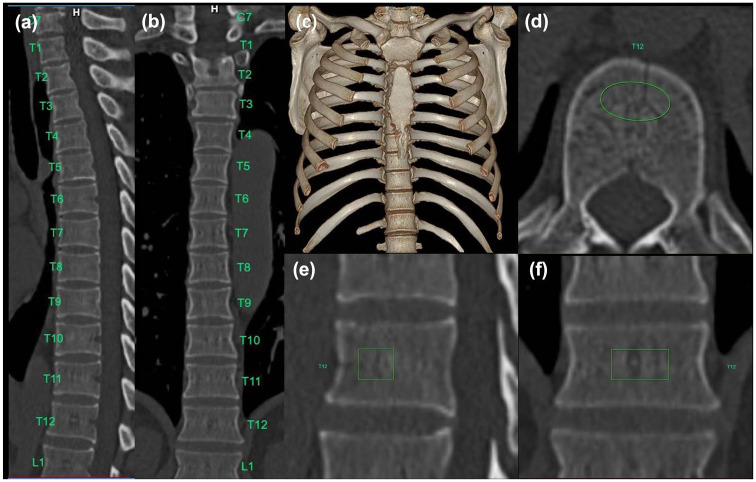

Methods: A total of 553 participants (353 men and 200 women) who underwent chest CT and DXA within 1 day were included. The attenuation values (HU) of the T7-12 vertebrae and L1 vertebra were obtained by AI. The effects of the clinical baseline data and attenuation values among the normal, osteopenia, and osteoporosis groups were compared. The correlation between attenuation and bone mineral density (BMD) values was analyzed, and the diagnostic performance of thoracic and first lumbar vertebrae attenuation values for diagnosing osteopenia or osteoporosis was further explored.

Results: The CT attenuation values of T7-12 and L1 vertebrae showed positive correlation with T-score (R = 0.58-0.61, p < 0.01). T12 attenuation >184.8 HU was 84.1% sensitive and 70.6% specific for distinguishing normal BMD, while T12 attenuation <146.2 HU was 61.4% specific and 75.6% sensitive for distinguishing osteoporosis from osteopenia. There were no significant differences between the T10-12 and L1 groups in distinguishing the normal, osteopenia, and osteoporosis groups. Moreover, the diagnostic efficacy among the T10, T11, T12, and L1 vertebral bodies was not statistically significantly different among the three groups.

Abstract Image